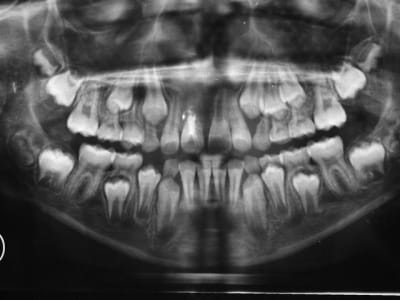

radio ce jour

aucune inflammation

acune douleur

aucune mobilité

pour mémoire le ttt MTA date de novembre

il me semble que la rhizalyse continue?

j'ai l'impression aussi,mais les angles de radio varient

tests de vitalite sur les 21-22?

RAS pr 21 et 22

le pb est effectivement d'avoir la mme angulation

je demanderai une pano en mai

à un an

âge de l'enfant : 9ans

la rhyzalyse de 11 semble bloquée par le ttt au MTA,ouf!(angle prévu incessamment sous peu ne vs inquiétez pas)

12 répond aux tests

mais...

21:

au froid,il a une sensation de chaleur...?

apex tjours pas fermé

qd faut y aller,faut y aller,à cette apexification?

rappel:choc avec expulsion et réimplantation de 11 en aoôut 2006 en milieu hospitalier

il a mainteant 9 ans et 5 mois

ankylose :ok, rien de nouveau

mes questions: les incisives du bas?

qu'en pensez vous?

il n'a pas de retard dentaire qd on regarde les autres dents mais les apex ne st pas fermés et les racines courtes surtout 31 41

ankyloses aussi?

aucun signes cliniques,repondent au froid

les incisives du bas:je ne crois pas que tu doives t'inquieter(touchees lors de la chute?),les apex sont presque a maturite,comme pour le haut

pour la longueur des racines,une pano n'est pas toujours le meilleur document

si vraiment tu veux eliminer le doute,une retro te sera plus utile

dernières radios

11 pas de changement semble t'il:pourvu que cela dure

21 l'apex se ferme malgré un MTA qui aurait pu aller un poil plus loin